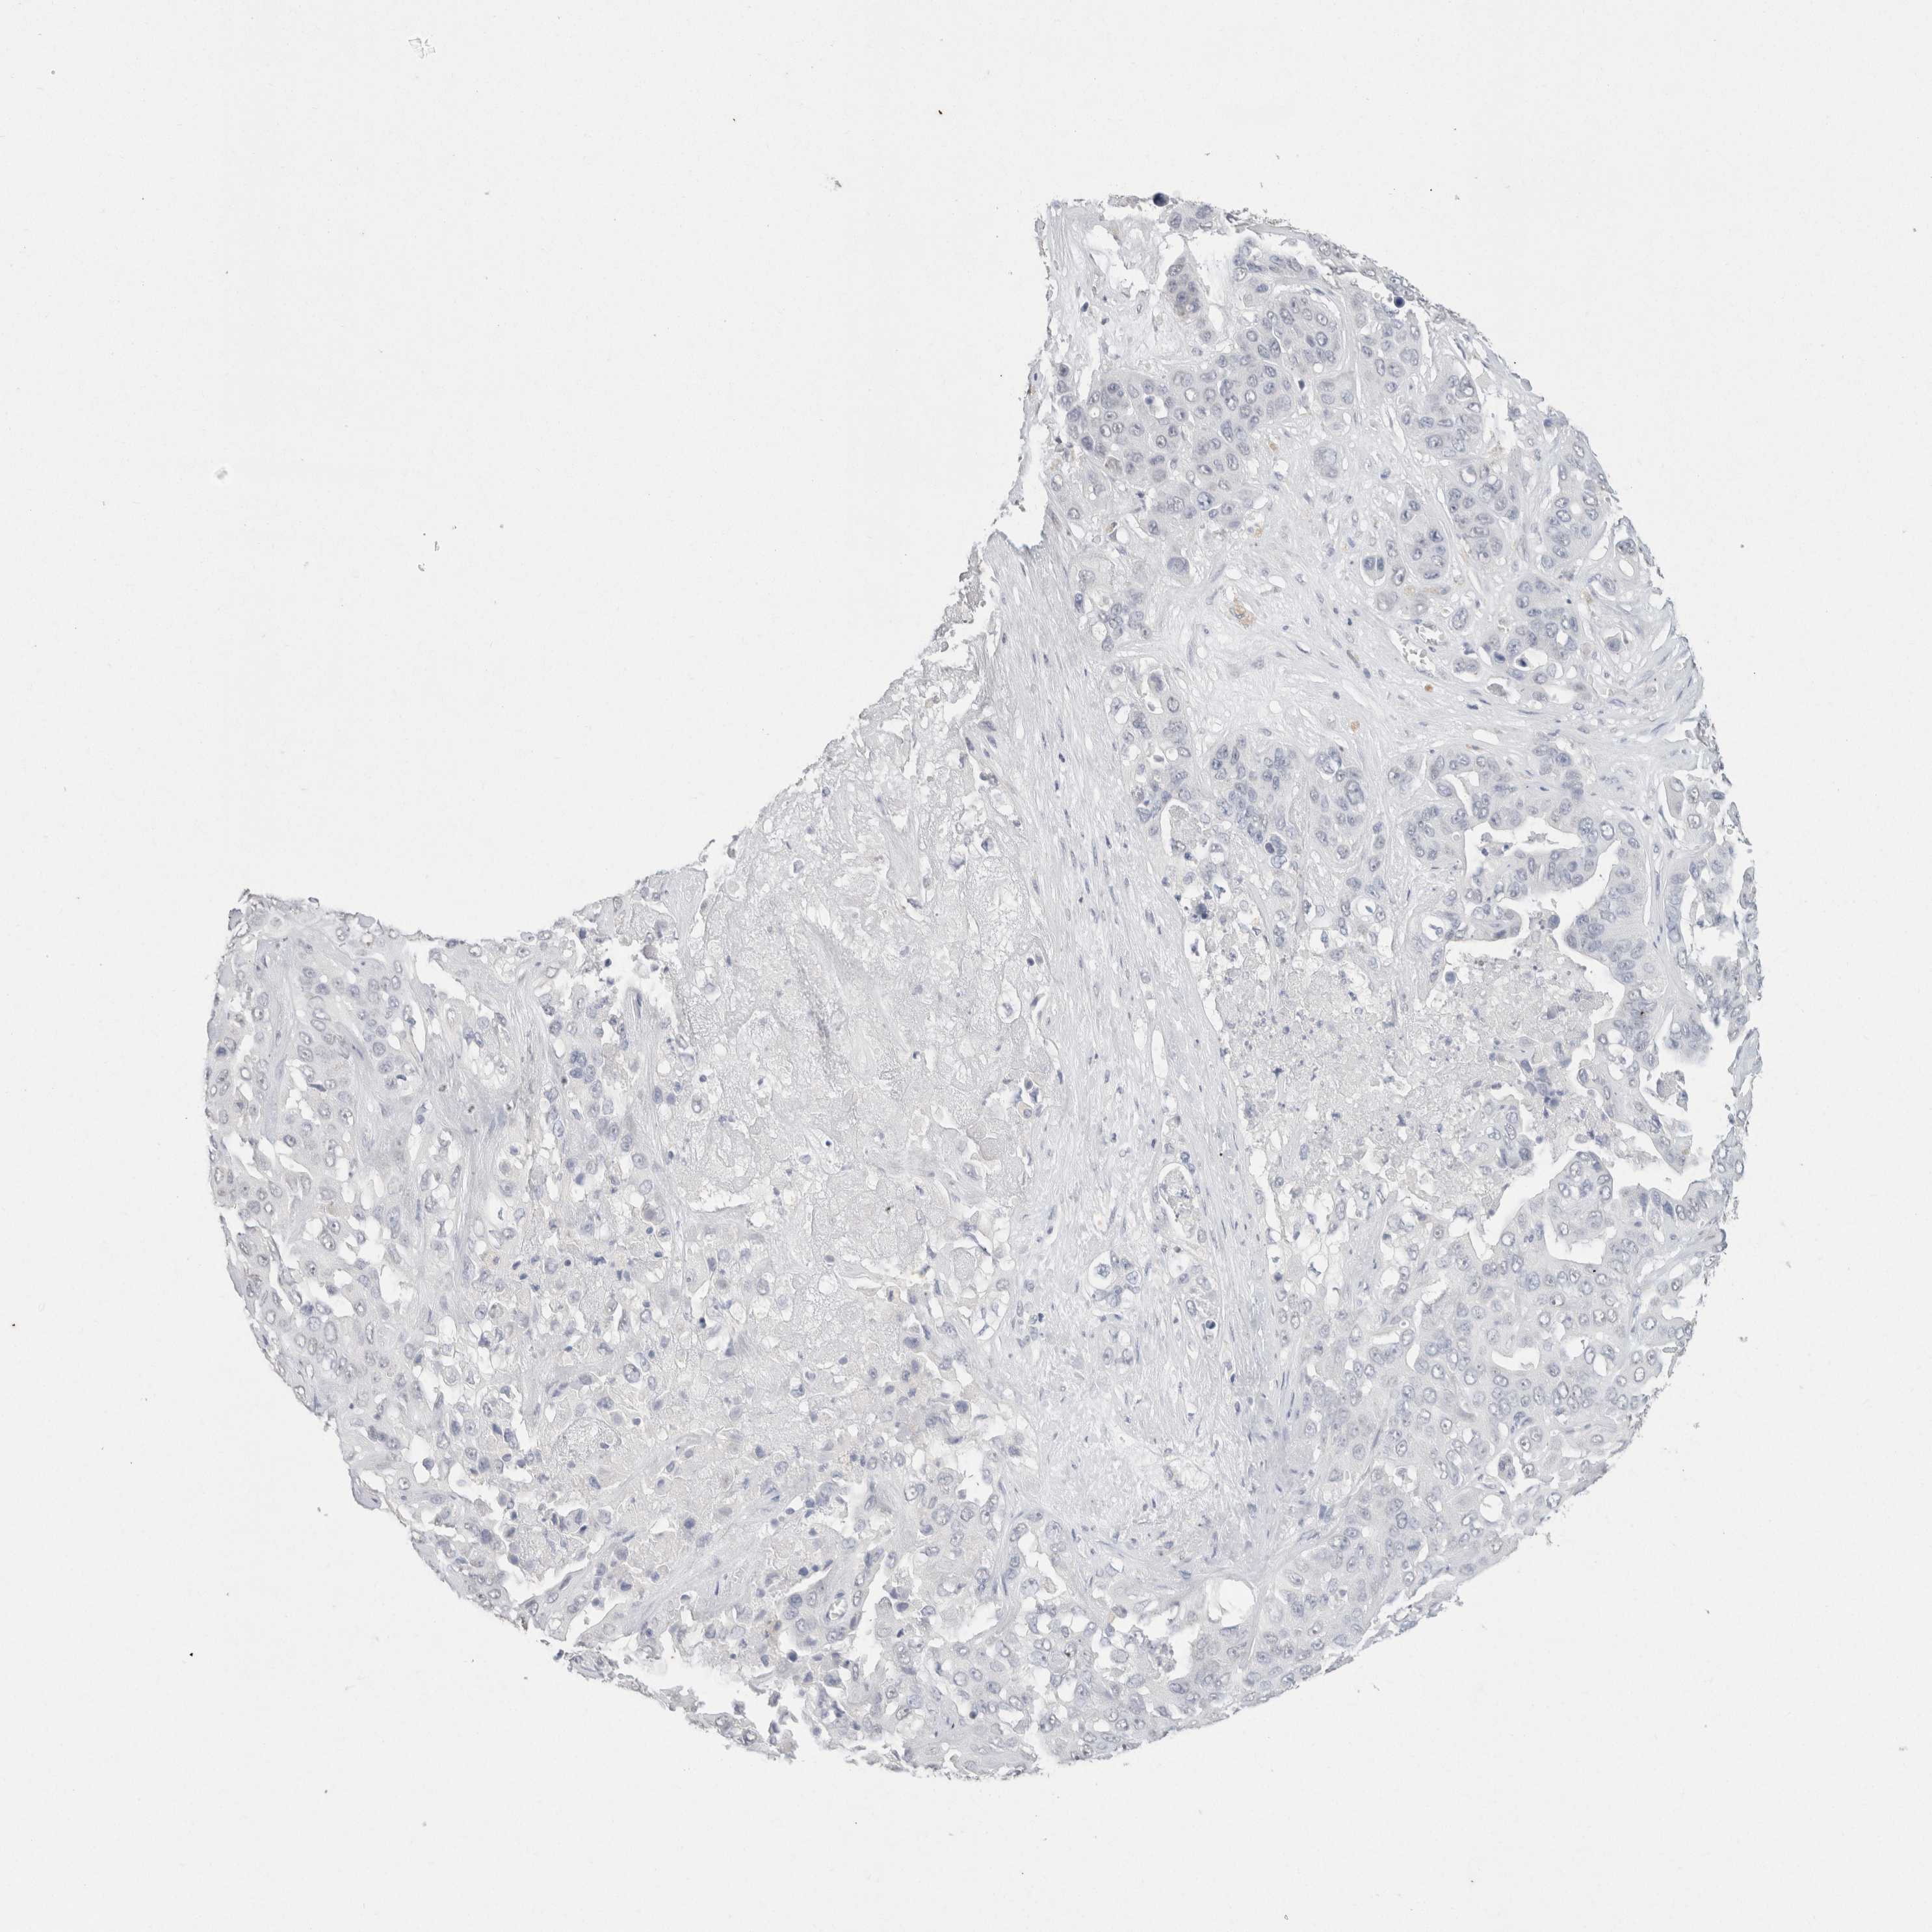

LIVER CANCER - Protein expressioni

A mouse-over function shows sample information and annotation data. Click on an image to view it in a full screen mode. Samples can be filtered based on level of antibody staining by selecting one or several of the following categories: high, medium, low and not detected. The assay and annotation is described here.

Note that samples used for immunohistochemistry by the Human Protein Atlas do not correspond to samples in the TCGA dataset.

Antibody stainingi

Antibody staining in the annotated cell types in the current human tissue is reported as not detected, low, medium, or high, based on conventional immunohistochemistry profiling in selected tissues. This score is based on the combination of the staining intensity and fraction of stained cells.

Each image is clickable and will lead to virtual microscopy that enables deeper exploration of all samples and also displays staining intensity scores, fraction scores and subcellular localization as well as patient and tissue information for each sample.

Antibody HPA050092

Antibody CAB025368

Staining

High

Medium

Low

Not detected

Intensity

Strong

Moderate

Weak

Negative

Quantity

>75%

75%-25%

<25%

None

Location

Nuclear

Cytoplasmic/membranous

Cytoplasmic/membranous,nuclear

Carcinoma, Hepatocellular, NOS

Cholangiocarcinoma